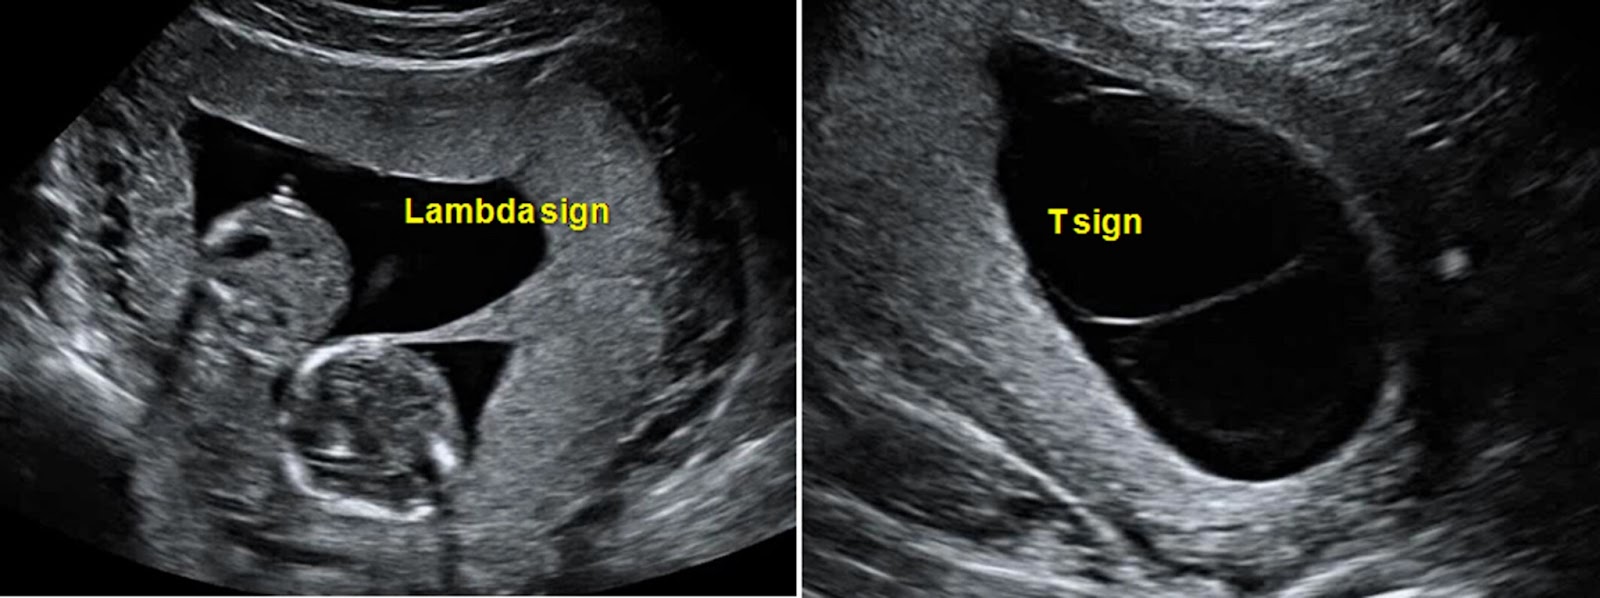

- Ultrasound: Essential for identifying multiple fetuses and determining chorionicity and amnionicity, with specific signs indicating dichorionic or monochorionic twins.

- Dichorionic Twins:

- Lambda Sign: Indicates twins with separate chorionic and amniotic sacs, seen as a λ-shaped separation on ultrasound.

- Monochorionic Twins:

- T-Sign: Suggests twins share a chorionic sac but have individual amniotic sacs, appearing as a T-shaped separation on ultrasound